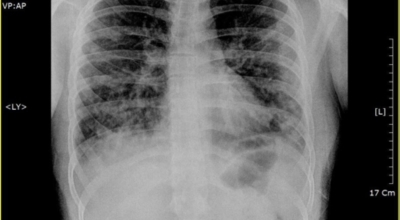

코로나 이후 기관지나 폐가 안좋아진 분 많으시죠. 코로나 이후 3년이 지난 지금도 여전히 코로나에 걸리는 분이 많고 재확진 사례도 주변에서 종종 찾아볼 수 있기에 계속 조심해야 합니다. 오늘은 폐에 좋은 음식 10 가지를 알려드리겠습니다.

건강한 폐를 위해서는 폐의 활동을 유지하는데 도움을 주는 건강에 좋은 음식을 섭취해야 합니다. 폐는 우리 몸에서 중요한 역할을 하는 것은 말할 필요도 없어요. 그러나 결국 폐는 공기 뿐만 아니라 대기 오염과 담배 연기 같은 유해한 요소를 흡입하게 되는데요. 이런 오염 물질은 천식, 기관지염, 낭포성 섬유증 또는 폐렴등의 호흡기 건강 문제의 위험을 증가시켜요.

세계보건기구인 WHO 에 의하면 2억 3천5백만 명이 천식으로 고통 받고 있으며 이는 진단 또는 치료가 부족한 상태이지요. 그렇기 때문에 폐 건강을 향상시키기 위해서는 폐에 좋은 음식을 섭취할 필요가 있어요.